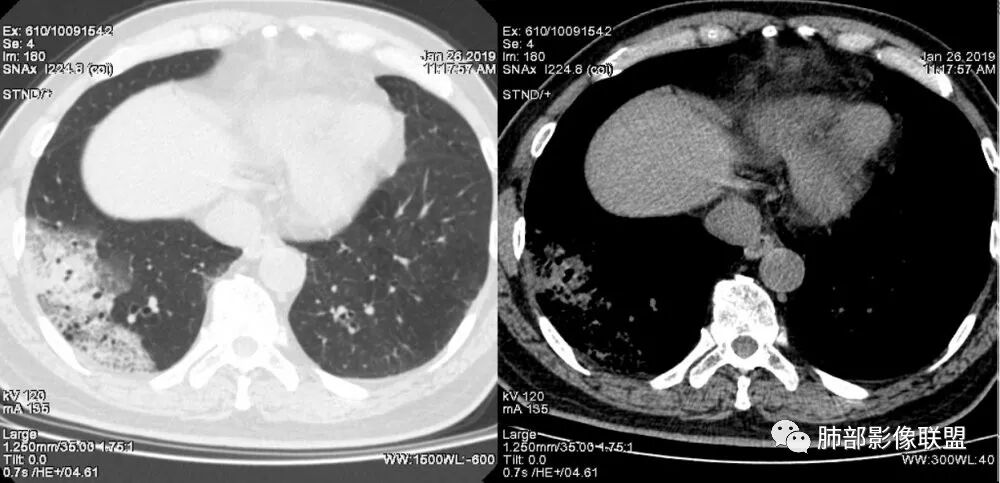

老年女性,右肺下叶沿胸膜下大片状高密度影,外周磨玻璃影,边界较清,内可见蜂窝征及支气管充气征,考虑肺炎型肺癌。

老年女性,咳嗽咳痰病史,右肺下叶大片磨玻璃实变影,胸膜下分布,支气管进入后扩张、僵直,磨玻璃影边界清楚,考虑粘液腺癌。鉴别肺炎。

右肺下叶基底段靠胸膜实变/磨玻璃混杂密度影,边界清楚,内见多发空泡(蜂窝样趋势改变?); 临床:咳嗽咳痰,无发热、胸痛; 考虑腺癌:无发热,感染性病变不首先考虑;部分层面形态类楔形,鉴别肺栓塞

中年女性,咳嗽咳痰。右肺下叶片状高密度影,部分实性密度,周围见边界清晰磨玻璃影,内见小空泡,实性区部分支气管堵塞,有重力效应,考虑肺炎型肺癌,建议查痰脱落细胞。

老年人,右肺下叶斑片状阴影,病灶有膨胀性,边缘可见磨玻璃影,其边界清晰,内见僵硬的支气管,部分支气管扩张,首先考虑占位性病变,粘液性腺癌可能。鉴别感染性病变,后者边缘多有收缩性改变或者平直,内部支气管走形自然。

中年女性,右肺下叶沿胸膜下大片状高密度影,实变加GGO,外朝内发展,边界较清,内可见蜂窝征及枯树征,考虑肺炎型肺癌。

右肺病灶,病灶较大,实性+周边ggo,边界清晰,胸膜下分布,长轴平行于胸膜,内部支气管充气征,因不发热,暂不考虑感染性病变,支持肺炎型肺癌。

老年女性,右下肺实变影,糊墙,外朝内发展,病灶里有小叶内间质增厚,周围边界清楚了GGO,支气管扩张明显,考虑粘液癌;不符合点,支气管扩张太厉害了,鉴别淋巴瘤。

患者中年女性,咳嗽咳痰就诊。胸部CT:右肺下叶后基底段片状实变影,由胸膜向内发展呈扇形,病灶里有小叶内间质增厚、蜂窝状影,周围边界清楚GGO,内可见扩张支气管,淋巴结无明显肿大。综合符合粘液腺癌。

1.本例病灶较大片混杂密度影,胸膜下分布为主(未沿着支气管分布),该分布特点可见于大叶性肺炎、干酪性肺炎、淋巴瘤及粘液腺癌等。可惜未提供增强扫描图像。

2.病灶示中央实变区,周围GGO,可见明显小叶间隔增厚,GGO边界清楚,应当考虑到恶性病变的可能性。肺炎因炎性水肿及渗出,影像上边界常模糊不清,注意早期粘液腺癌可出现似清非清的边界。粘液腺癌因粘液成份较多,密度一般偏低,纵隔窗病灶常会消隐或范围会明显缩小,这不同于炎性实变。

3.病灶内支气管走形略显僵直,侧支少(粘液阻塞),也符合肺腺癌的枯树枝征。而大叶性肺炎的支气管是管壁光整、通畅、自然,结核的支气管常常壁增厚,甚至狭窄后扩张;